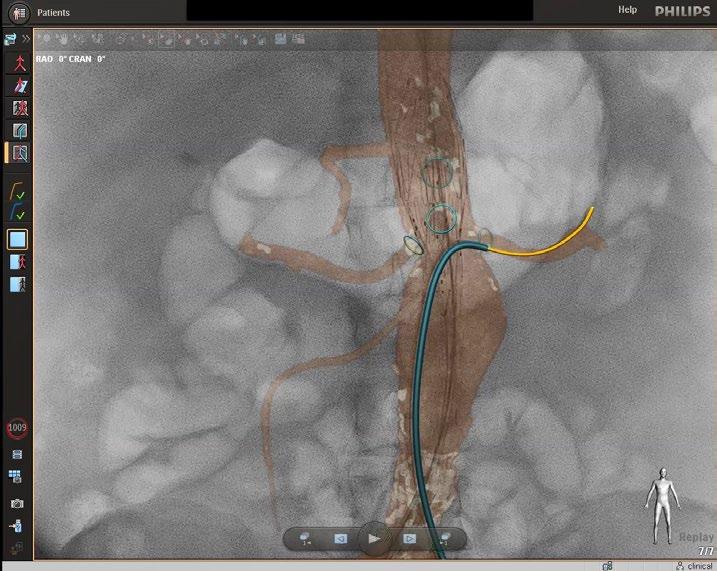

Endovascular repairs are done in a hybrid cardiovascular operating room with advanced imaging equipment, a fluoroscopy unit and traditional operating suite. At UMass Memorial Medical Center, the hybrid OR is also equipped with Fiber Optic RealShape (FORS) technology. Surgeons there were the first in the nation to use FORS for a complex endovascular aortic aneurysm repair (EVAR). The technology gives operators better imaging and more flexibility in maneuvering endovascular guidewires and catheters for EVAR, while also reducing dependence on fluoroscopy.

A new technology developed by Philips dramatically improves visibility while also reducing dependence on fluoroscopy. In 2021, UMass Memorial Medical Center vascular surgeons became the first in the nation to use FORS, a technology that generates realtime images of endovascular devices by refracting light through optical fibers. Only two other hospitals in the U.S. and three outside the country are currently using it.

Instead of the ionizing radiation of fluoroscopy, FORS technology uses light refracted through optical fibers to provide 3D tracking of endovascular guidewires, catheters and devices. FORS technology has the potential to reduce

a patient’s radiation exposure by as much as 75% during endovascular complex aortic aneurysm repair.

Imaging advantages

In addition to reducing the need for fluoroscopy, FORS technology enhances the visibility as the operator moves devices through the arteries. The real-time images produced are three dimensional, so the EVAR team can view progress and movement from any angle. The technology also allows for zooming in and having multiple projections on-screen at once.

“This enables me to always keep the full extent of the guidewire in my field of vision,” Schanzer said. “Then I can advance the FORS catheter over the wire to get it in position. The FORS system shows which portion of the

guidewire or catheter is in front of the other, making all endovascular interventions easier and safer.”

The FORS images are displayed on top of, and in alignment with, anatomical patient images created through digital subtraction angiography (DSA) or computed tomography (CT), both of which are black and white. With DSA or CT

images alone, it can be difficult to determine the exact placement of the catheter, but with FORS technology, it can be seen in color in the foreground.

“The system is very intuitive and truly represents a new era in device guidance,” Schanzer said, adding that having a color image has an additional benefit. “Until I started using FORS, I hadn’t realized how much operator fatigue there is when you’re only looking at different shades of gray to visualize everything. It’s become very apparent to me that the bright yellow and blue on top of the gray background really decreases that strain, especially when you’re looking at previous stent grafts and wires.” ◼